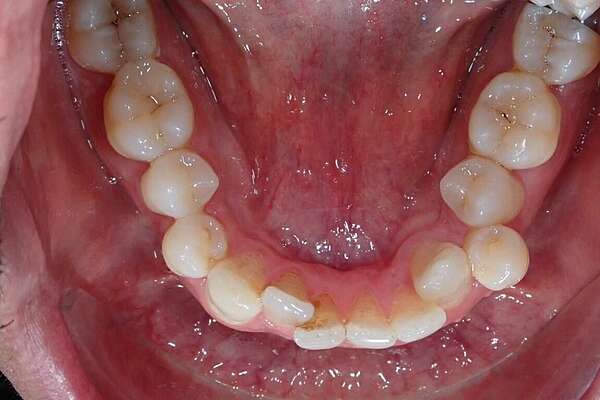

Important encombrement traité par gouttières